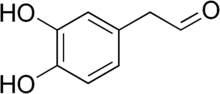

Catecholaldehyde hypothesis

The enzyme monoamine oxidase (MAO) plays a central role in the metabolism of the neurotransmitter dopamine and other catecholamines. The catecholaldehyde hypothesis argues that the oxidation of dopamine by MAO into 3,4-dihydroxyphenylacetaldehyde (DOPAL) and hydrogen peroxide and the subsequent abnormal accumulation thereof leads to neurodegeneration. The theory posits that DOPAL interacts with alpha-synuclein and causes it to aggregate.[86][87]